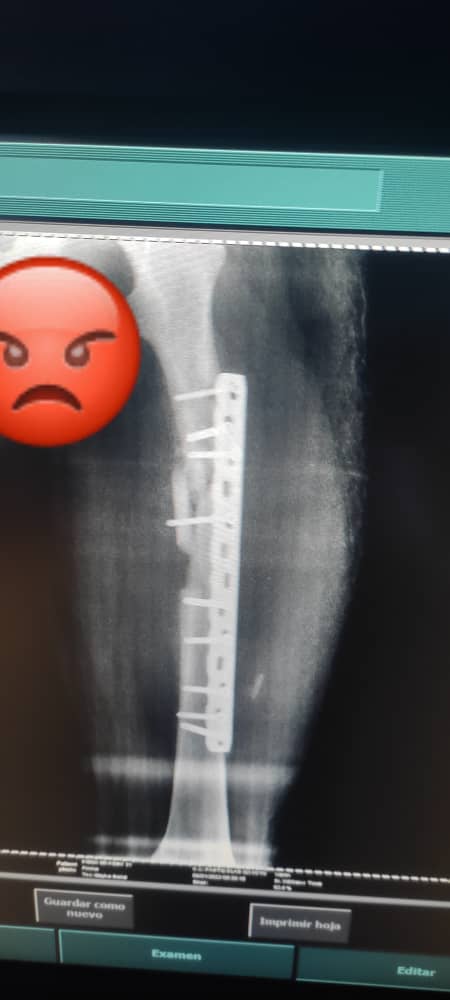

Cuenta el agraviado que durante el proceso de recuperación, “presenté molestias, al tiempo me tuve que volver a operar porque el Dr. hizo mal su trabajo ya que me dejó el hueso fuera de su lugar, tuve perdida ósea y la platina quirúrgica no es nueva, es usada y además presenta las siglas del MPPS; para mí, esto es un robo a la nación ya que yo pagué por una platina nueva, en una clínica privada, además no me colocó la platina adecuada a mí fractura, los tornillos no son los diámetros y están cortados con alicate, necesito que la fiscalía se aboque al caso ya que no me dan respuesta alguna sobre esto”.